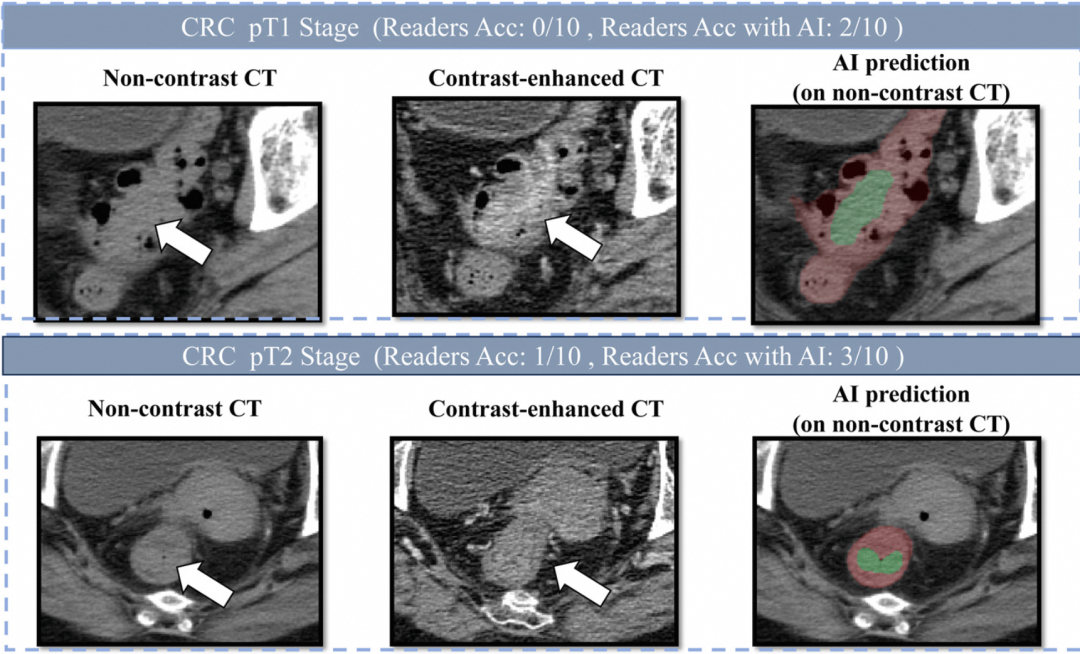

所以当研究团队邀请10位医生参与人机对照实验时,医生们甚至都有点茫然——这超出了他们的临床经验。

延续前面两个癌种的技术积累,DAMO COCA模型采用了"先定位、后诊断"的两阶段深度学习架构:第一步精确分割出形态复杂的肠道器官——这一步对AI本身就是挑战;第二步对可疑区域逐一精细判断。为了提升对早期小肿瘤的识别能力,团队还针对小于3厘米的病灶做了重点训练。

训练数据的构建更是一场硬仗。医生没法直接在平扫CT上标注肠癌——因为人眼看不清。团队的办法是:先请医生在增强CT(注射造影剂后对比度更高的影像)上精确勾画肿瘤位置,再通过图像配准技术"投射"到平扫CT上。